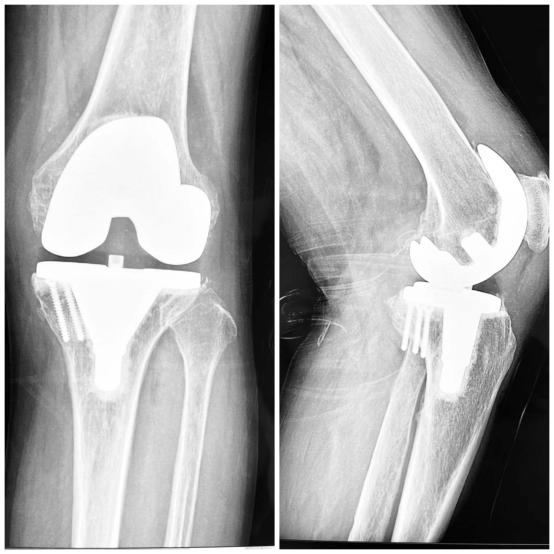

兰大二院西固医院骨科团队,于2021年12月31日开展西固区首例导航(IKPAS)下膝关节膝关节置换术(TKA),该患者严重膝关节畸形,生活重度受限,术后患者畸形完全纠正,康复良好,生活质量明显提高。导航(IKPAS)下关节置换技术为当今先进手术技术,此技术为严重膝关节畸形患者力线纠正带来了福音。